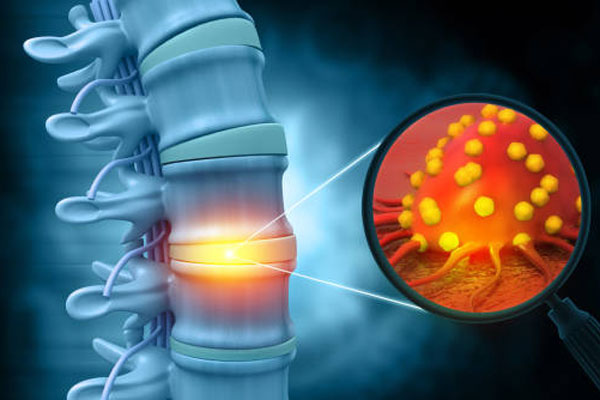

Trauma management including fractures and complex injuries, joint replacement surgeries for knee, hip, and shoulder with advanced recovery techniques, treatment of sports injuries including ligament repair and cartilage treatment, care for spine disorders such as scoliosis, herniated discs, and degenerative spine diseases, and orthopedic oncology surgery for bone tumors and musculoskeletal cancers.

Orthopaedics focuses on treating injuries and disorders of the musculoskeletal system including bones, joints, muscles, tendons, ligaments, and nerves, enabling better mobility and daily activity.